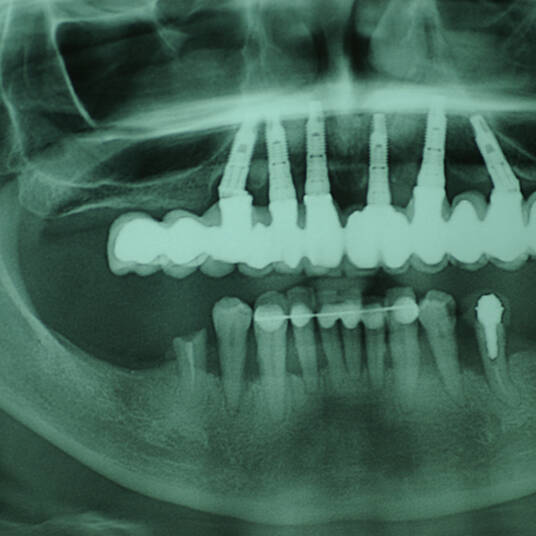

Na Clínica Pontes Odontologia, somos referência em implantes dentários em Fortaleza, oferecendo tratamentos de alta qualidade e tecnologia de ponta. Os implantes dentários são estruturas de titânio posicionadas cirurgicamente no osso maxilar ou mandibular para substituir as raízes dos dentes ausentes. Essa técnica permite a fixação de próteses personalizadas, restaurando a função mastigatória, a estética e a autoestima dos nossos pacientes.

Utilizamos a tecnologia CAD CAM, um sistema avançado que possibilita a confecção precisa das próteses dentárias diretamente sobre os implantes. Esse método inovador garante um ajuste perfeito, um resultado estético superior e proporciona muito mais conforto e durabilidade. Com o CAD CAM, nossos pacientes contam com um processo mais rápido e previsível para alcançar o sorriso desejado.